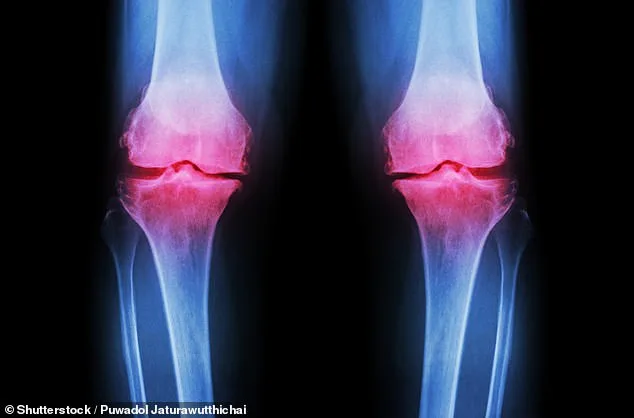

Osteoarthritis occurs when protective cartilage on joints wears down, leading to pain, stiffness, and reduced mobility. While joint damage is a normal part of life, the body typically repairs it. However, excessive stress from high-impact exercise and poor nutrition can overwhelm this natural process. Factors such as genetics, obesity, repeated stress on joints, and injuries all contribute to cartilage degradation. Post-traumatic osteoarthritis, for example, can result from fractures that affect joints, altering their mechanics and accelerating cartilage breakdown.